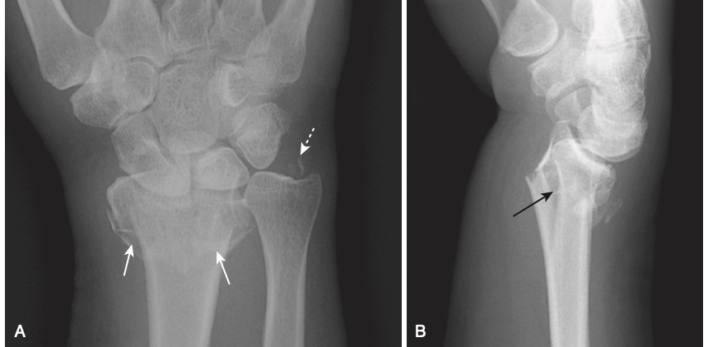

Gãy xương thuyền (Scaphoid fractures)

- Thường gặp

- Nghi ngờ gãy xương thuyền trên lâm sàng nếu đau ở hõm lào giải phẫu (anatomic snuff box) sau khi ngã chống tay.

- Tìm đường thấu quang mỏng trên phim (Tư thế xương thuyền: cổ tay duỗi 30⁰, nghiêng trụ 20⁰) (Hình 14).

- Gãy ngang eo xương thuyền có thể dẫn đến hoại tử vô mạch cực trên xương thuyền.

- Do đặc trưng phân bố mạch máu, gãy ngang eo xương thuyền ở cổ tay làm gián đoạn nguồn cung cấp máu đến cực trên, trong khi phần còn lại của xương cổ tay tiếp tục trải qua quá trình luân chuyển xương, mất khoáng. Kết quả là sự gia tăng tương đối rõ ràng về đậm độ xương của phần trên không được phân nuôi dưỡng so với phần còn lại của xương (Hình 15).